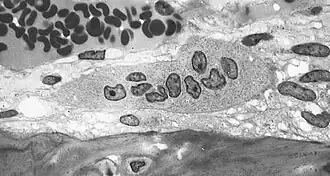

Light micrograph of an osteoclast displaying typical distinguishing characteristics: a large cell with multiple nuclei and a "foamy" cytosol. -

Light micrograph of osteoblasts, several displaying a prominent Golgi apparatus, actively synthesizing osteoid containing two osteocytes. -